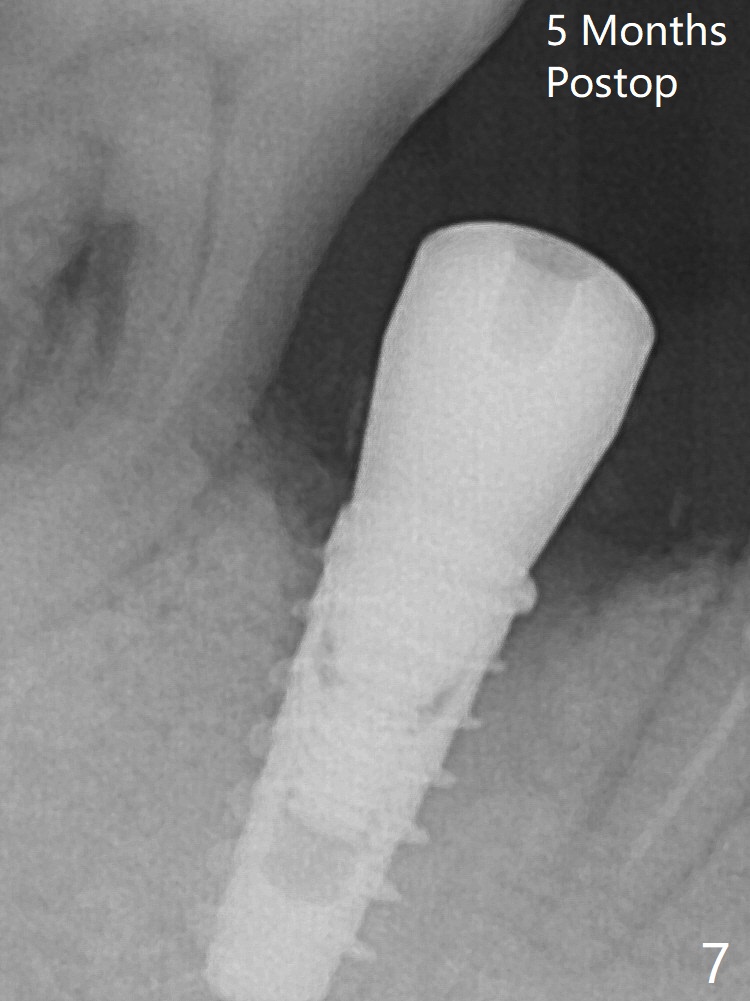

Final implant (Fig.5: 4x9 mm; red dashed line: socket) is placed 4 mm subgingival (supracrestal buccal; infracrestal lingual); Vanilla graft placed buccodistal (*). One month later, the abutment dislodges. The patient insists upon no provisional so that he can masticate on the right side, since there is no functional molars on the left side. A 4.5x3 mm healing abutment is placed. The implant appears to have osteointegrated 5 months postop (Fig7). A 4.5x5.7(4) mm pair abutment is placed for impression. The crown is loose 2.5 months post cementation (8.5 months postop); there is bone loss around the implant (Fig.8 *).